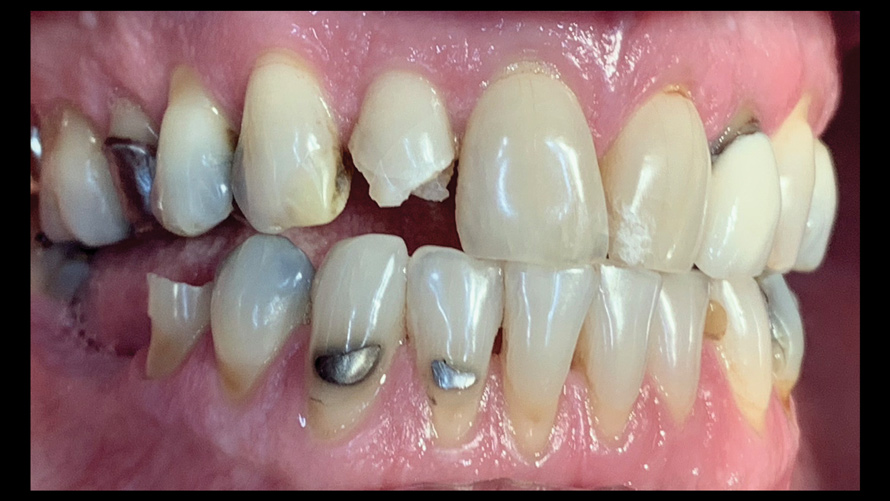

(5.) Side-by-side comparison of a contemporary smartphone camera image and a DSLR camera system image.

Figure 5

(6.) Side-by-side comparison of a contemporary smartphone camera image and a DSLR camera system image.

Figure 6

For most dental clinicians and technicians, the acquisition of professional-level photographs with a DSLR camera requires a steep economic investment and possesses a shallow learning curve. The time commitment and nebulous return on investment are certainly potent deterrents to the incorporation of these systems into daily practice. While remaining cognizant of the need for photographic documentation, the dental field has witnessed an increase at the low end of the dental photography continuum through the use of the ubiquitous smartphone as a proxy for the larger and more expensive DSLR camera setups. Most smartphones will allow the user to customize and control the elements of the exposure triangle via the internal camera settings or by means of a third-party application (Figure 4); however, the diminutive nature of the lenses, apertures, and sensors of these devices makes the necessary attainment of light problematic. When this is coupled with low-capacity native light output on the subject being photographed, the resulting images are often distorted, low-resolution, and possess inconsistent reproduction of color and detail, which renders them unacceptable for documenting patient treatment and collaborating with the laboratory (Figure 5 and Figure 6).